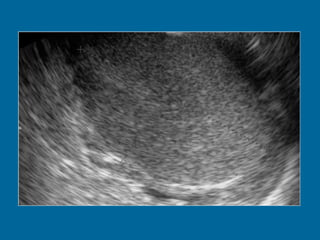

Transverse US scan of the testis shows a normal transmediastinal artery (arrow) as a linear hypoechoic band. Color Doppler flow US (not shown) revealed flow through the vessel.

Transverse US scanof the testis shows a normal transmediastinal artery (arrow) as a linear hypoechoic band. Color Doppler flow US (not shown) revealed flow through the vessel.